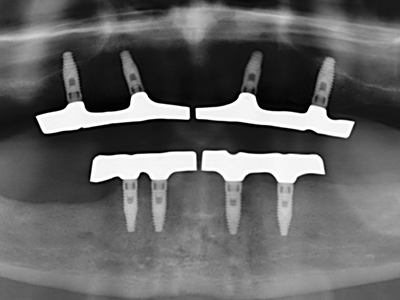

Фиг. 11: Следоперативната панорамна снимка показва вертикалната аугментация и синус лифта.

Фиг. 12: След шест месеца на заздравяване, алвеоларният гребен е добре оразмерен триизмерно.

Препарацията на латерално ламбо по време на външен синус лифт е предизвикателство, особено за имплантолози с малък опит в хирургията. Отделянето на костното покритие на синуса без да бъде наранена лежащата отдолу Шнайдерова мембрана е само част от операцията – след установяване на подходящ достъп, линията на мембраната на синуса трябва внимателно да бъде повдигната, за да се направи място за материалите за аугментация или имплантите. Пиезохирургията е полезна за тази индикация по два начина: могат да се използват накрайници с диамантено покритие за избирателна костна аблация и едновременно с това, лежащата отдолу мукозна мембрана остава непокътната, когато процедурата е извършена прецизно. Ултразвуковите честоти също допринасят за отделяне на мукозната мембрана без усложнения – честотите се предават в пространството между мукозната мембрана и синуса чрез специални накрайници със заоблени ръбове (Cassetta, Ricci et al. 2012, Pereira, Gealh et al. 2014) (Rickert, Vissink et al. 2013). В резултат на това, не е изненадващо, че текущите доклади за външен синус лифт оценят положително пиезоелектрическите апарати, както и употребата на импланти с набраздени повърхности и костозаместителни материали. (Wallace, Tarnow et al. 2012).